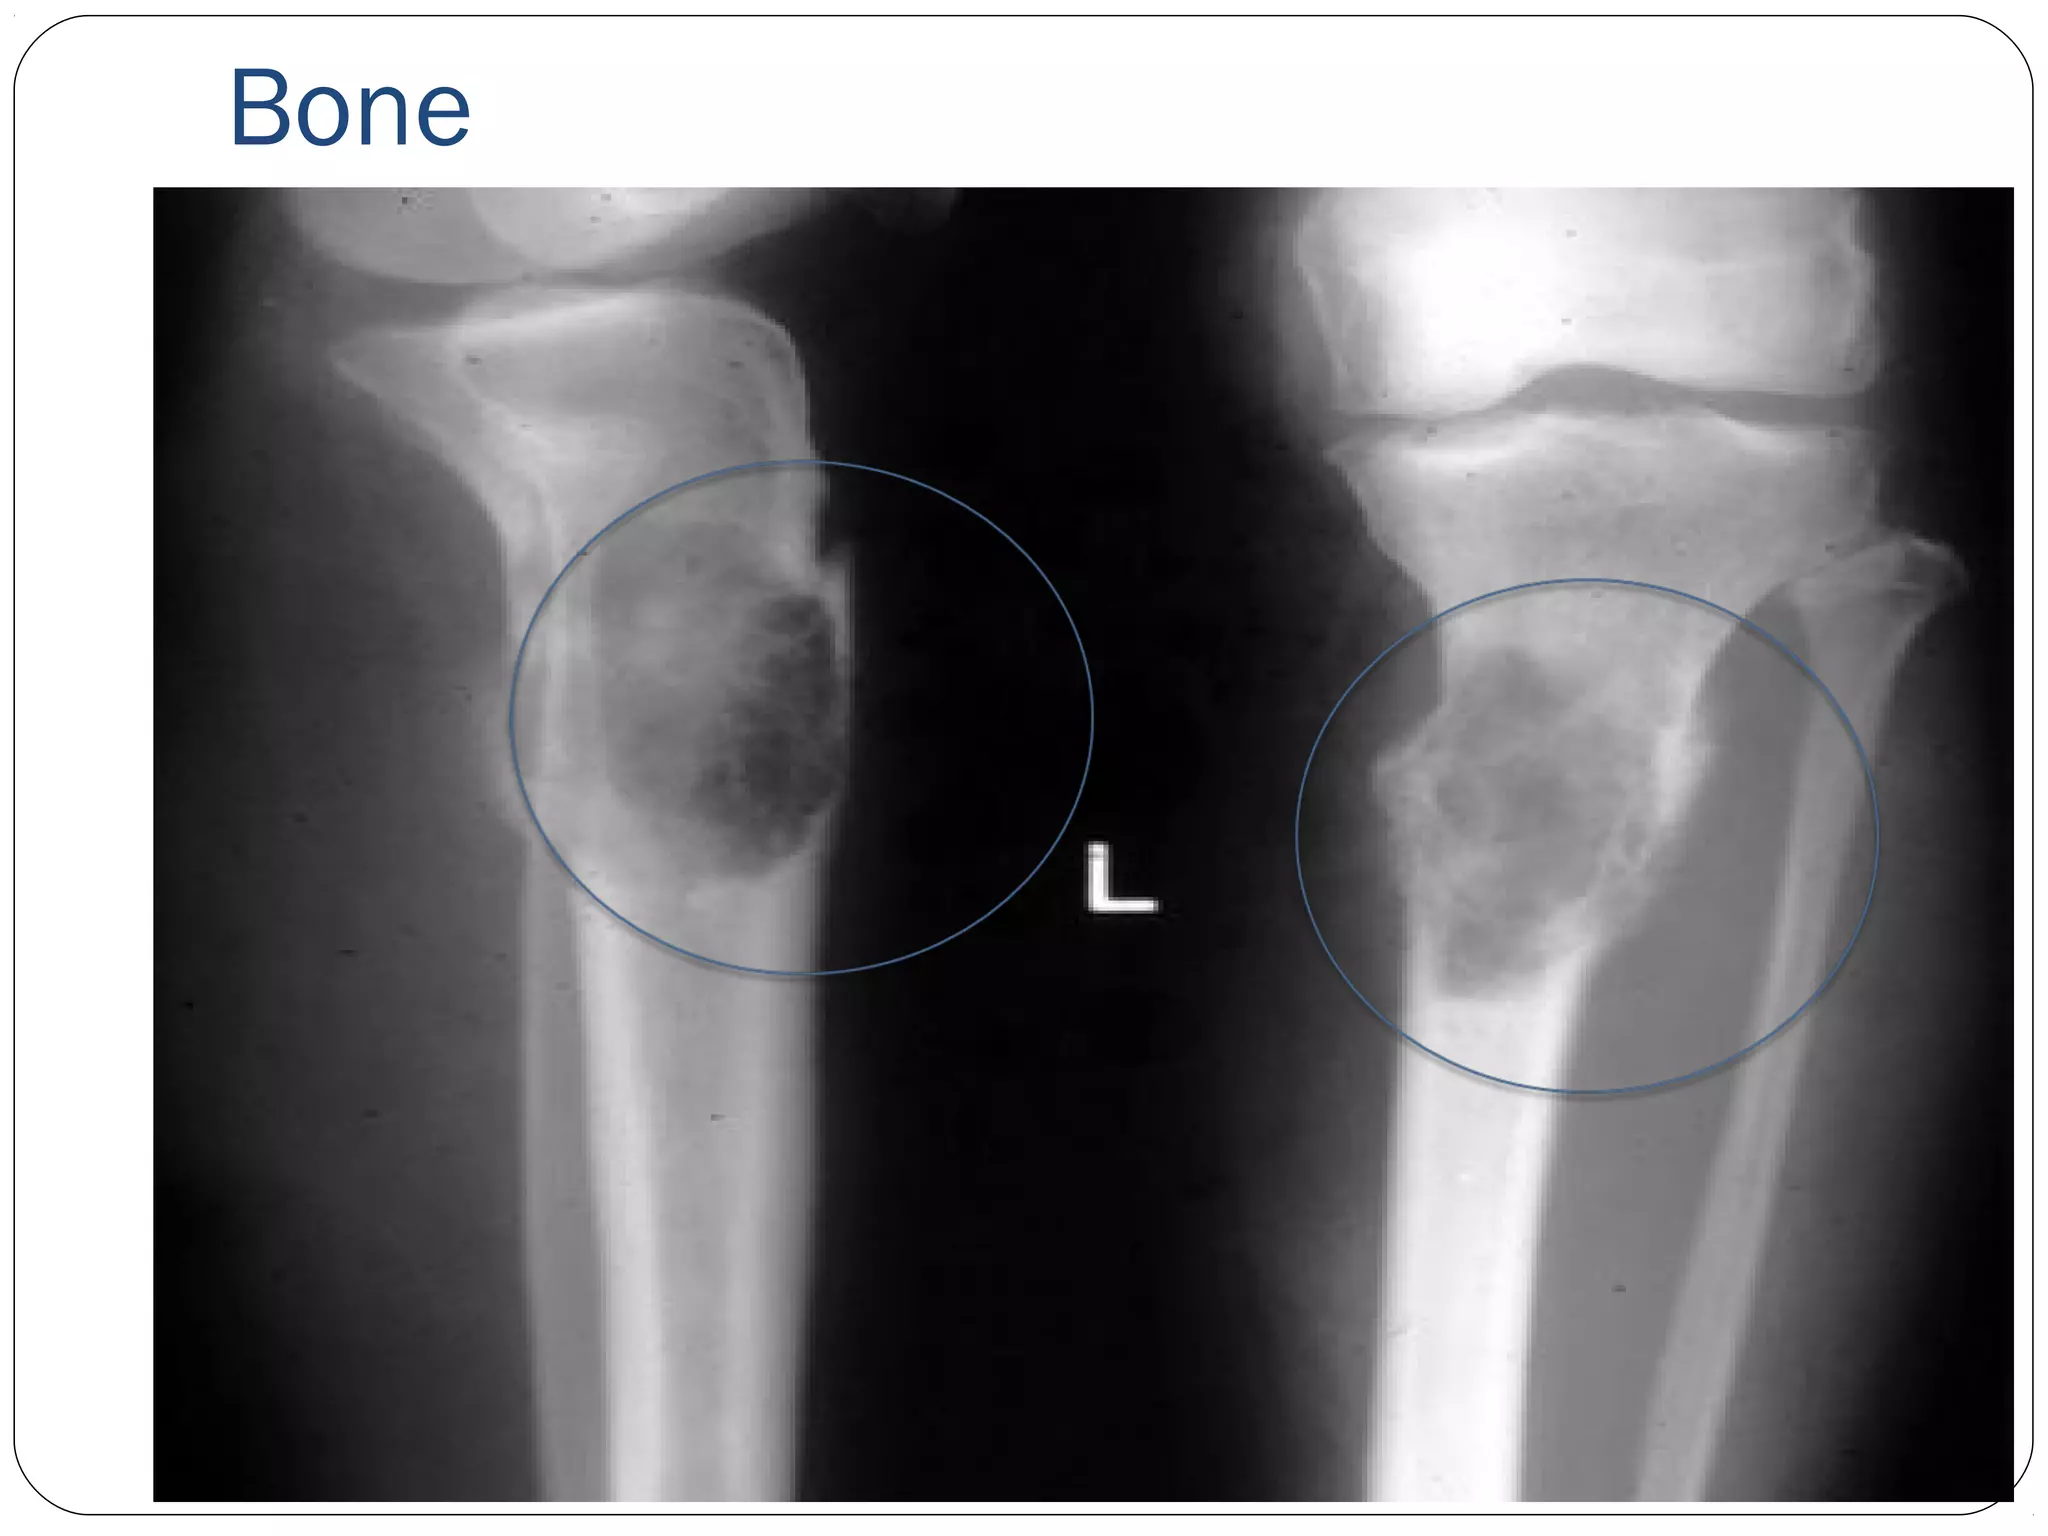

Bone

• #27 It takes 30-35% loss of bone before osteoporosis can be diagnosed on radiograph

• #28 Metastic cancer in the tibia and fibula